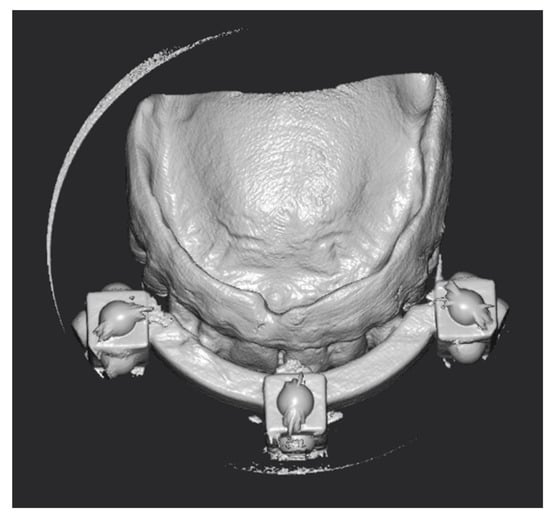

2.1. Surgical Guide Design

2.2. Surgery